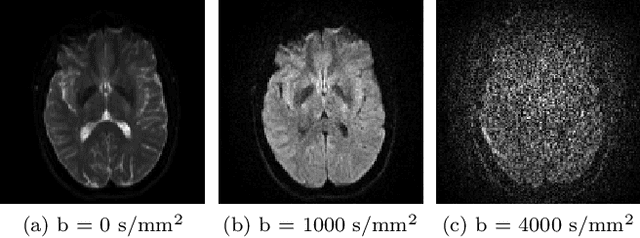

Abstract:Diffusion weighted imaging techniques permit us to infer microstructural detail in biological tissue in vivo and noninvasively. Modern sequences are based on advanced diffusion encoding schemes, allowing probing of more revealing measures of tissue microstructure than the standard apparent diffusion coefficient or fractional anisotropy. Though these methods may result in faster or more revealing acquisitions, they generally demand prior knowledge of sequence-specific parameters for which there is no accepted sharing standard. Here, we present a metadata labelling scheme suitable for the needs of developers and users within the diffusion neuroimaging community alike: a lightweight, unambiguous parametric map relaying acqusition parameters. This extensible scheme supports a wide spectrum of diffusion encoding methods, from single diffusion encoding to highly complex sequences involving arbitrary gradient waveforms. Built under the brain imaging data structure (BIDS), it allows storage of advanced diffusion MRI data comprehensively alongside any other neuroimaging information, facilitating processing pipelines and multimodal analyses. We illustrate the usefulness of this BIDS-extension with a range of example data, and discuss the extension's impact on pre- and post-processing software.